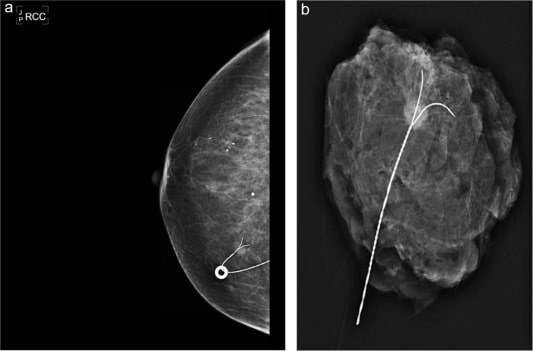

ماموگرافی ماموگرافی

• ماموگرافی روتین

• بزرگنمایی و Focal Compression

• ماموگرافی پستان های دارای پروتز